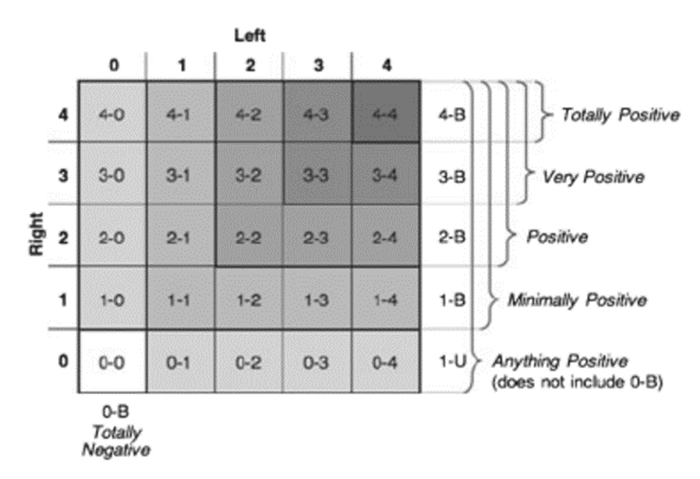

(2)ETUDES方案[22]:2009年又有学者提出了利用肺部超声B线联合脑钠肽(brain natriuretic peptide,BNP)诊断急性心源性肺水肿的ETUDES(emergency thoracic ultrasound in the differentiation of the etiology of shortness of breath)方案,该方案将双侧胸腔分为8个区域,记录各区域B线数目(图 31),双侧胸壁出现3条以上B线的区域越多,心源性肺水肿可能性越大。如每侧胸壁有3个以上区域均有3条以上B线出现则诊断心源性肺水肿可能性超过90%(图 32)。

| 图 32 4-B指双侧胸壁(单侧各四个区域)所有区域均出现3条以上B线;3-B指每侧胸壁(单侧各四个区域)至少有3个区域均出现3条以上B线;2-B指每侧胸壁(单侧各四个区域)至少有2个区域均出现3条以上B线;1-B指每侧胸壁(单侧各四个区域)至少有1个区域出现3条以上B线;0-B指所有区域均未出现3条以上B线;1-U指仅有单侧胸壁区域内出现3条以上B线 |